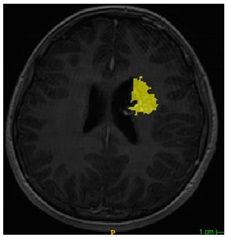

Three cases from the NTUH dataset showing representative results of different models were shown in Table 2, Table 3 and Table 4. The overall dice scores of these networks on the NTUH dataset ranged from 0.33 (DeepMedic) to 0.51 (V-Net). Table 5 shows the detailed performance of each network tested with the NTUH dataset.

Table 2.

Predictions with low dice scores.

Table 3.

Predictions with average dice scores.

Table 4.

Predictions with high dice scores.